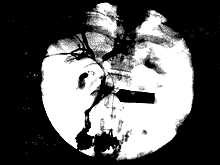

1.2.2靶血管的药盒植入术:在胆道内支架植入术后7~10天,行靶血管的药盒植入术,选择股动脉或锁骨下动脉入路,采用Seldinger穿刺技术及导管超选技术,使导管置入肿瘤供血管(肝固有动脉,肝总动脉,胰十二指肠动脉等)。药盒植入皮下,缝合皮肤(如图3)。之后按肿瘤生物学特性及药代动力学

图3 胆管支架置入后,行PCS术。

(箭头所指为PCS导管)